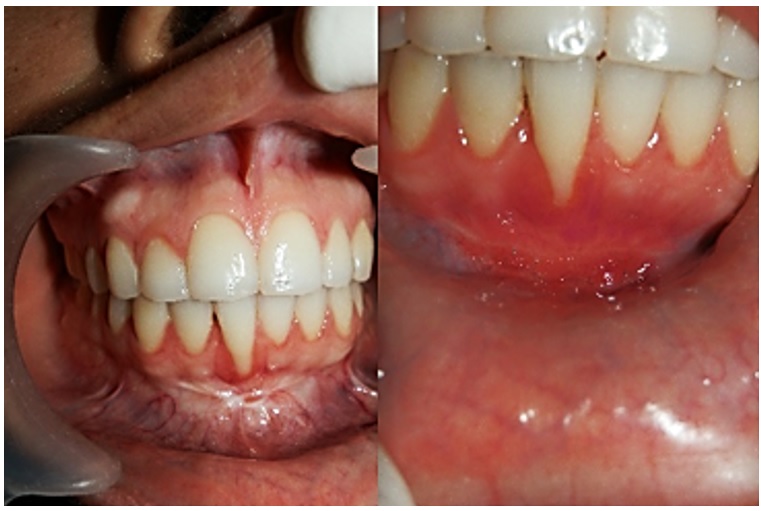

Una mujer de 28 años de edad acudió a consulta, porque presentaba gingivitis marginal generalizada con pérdida de inserción preexistente en la zona del incisivo central derecho (diente 41, según la nomenclatura dígito 2 de la Federación Dental Internacional, sistema ISO 3950) e inserción anómala del frenillo labial inferior. La paciente estaba inconforme con su estética en el sector anteroinferior. En el examen se observó un vestíbulo poco profundo y poca resiliencia, frenillo labial inferior casi imperceptible, eritema en la encía marginal y recesión marcada en el diente 41. No se hallaron bolsas periodontales ni evidencia de encía insertada insuficiente (figura 2). Radiográficamente se observaba normalidad en las estructuras. Se clasificó como recesión clase II según Miller y se evaluó la necesidad de implementar una terapia etiotrópica periodontal a través del raspado y alisado radicular y profilaxis antes de cualquier consideración quirúrgica. Luego de la fase etiotrópica periodontal, se decidió manejar el caso quirúrgicamente para corregir la retracción gingival y controlar el riesgo de complicaciones mayores.

Una mujer de 34 años de edad asistió a consulta por presentar gingivitis marginal localizada con pérdida de inserción preexistente en la zona del incisivo central izquierdo (diente 31) e inserción anómala del frenillo labial inferior. Estaba inconforme con la apariencia de su encía en el sector anteroinferior. Se observó un vestíbulo poco profundo con poca resiliencia, frenillo labial inferior sobreinsertado en encía adherida y recesión marcada en el diente 31. En el sondeo no se encontraron bolsas periodontales o evidencia de encía insertada insuficiente (figura 3). Se clasificó como recesión clase I, según Miller. Se evaluó la necesidad de implementar una terapia etiotrópica periodontal a través del raspado y alisado radicular y profilaxis antes de cualquier consideración quirúrgica. Se decidió efectuar el procedimiento quirúrgico para corregir la retracción gingival y controlar el riesgo de complicaciones.